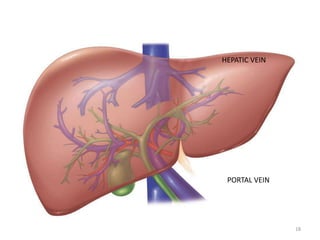

PORTAL VEIN

HEPATIC VEIN